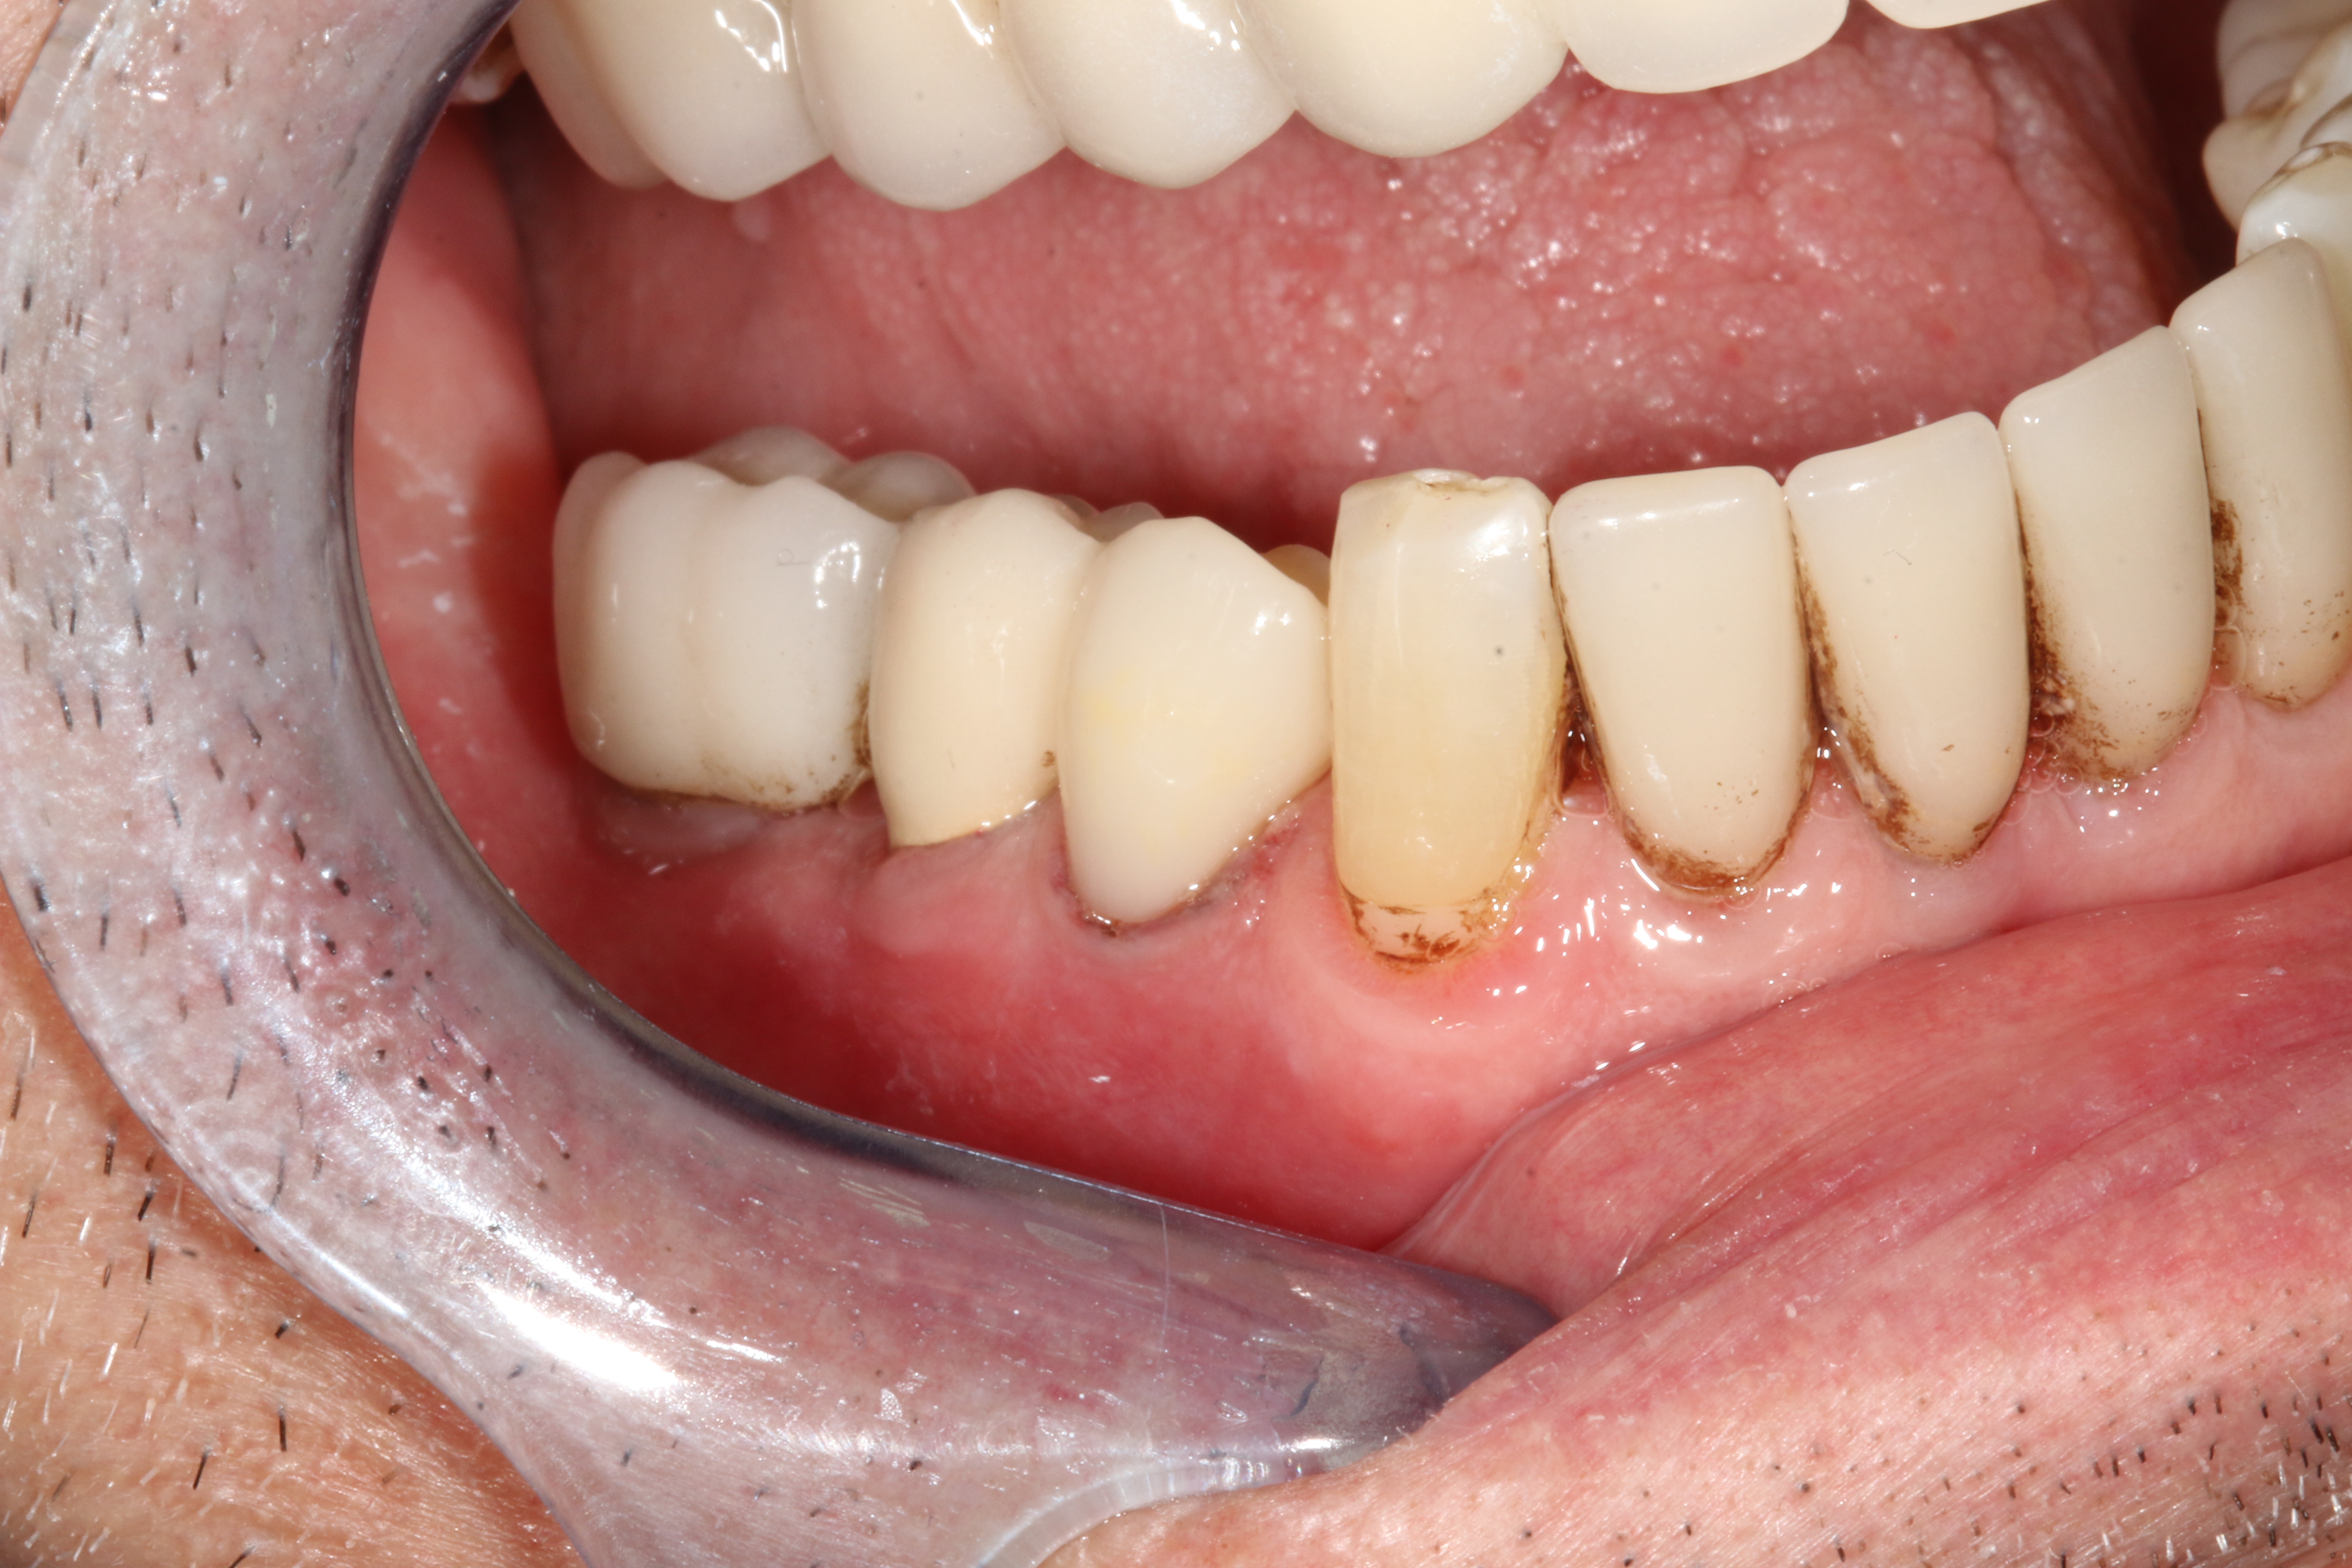

A 71-year-old man presented with acute pain in tooth No. 29 that was spontaneous, unresponsive to vitality testing, and sensitive to percussion. He was referred to an endodontist for treatment of acute apical periodontitis due to the non-vitality of the nerve. Because of the multiple restorations and lingual decay of the tooth, enamel and dentin were compromised, causing the tooth to be biomechanically at high risk and requiring an eventual post-and-core and crown (Figure 1 and Figure 2). Endodontic care included nonsurgical intracanal therapy and creating room for a post space.

Fig 2. Preoperative view of tooth to be restored shows defective Class 5 restoration that unfortunately was mirrored on the lingual gingival margin.

Figure 2